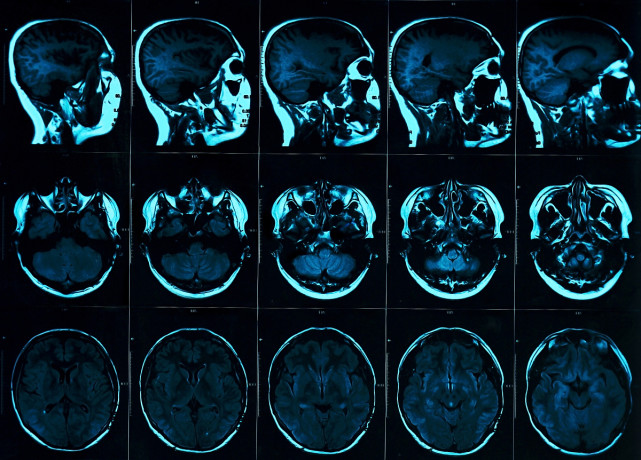

单单昨晚,内科急诊收治的脑出血、脑梗死、心肌梗塞病人多达十几人,看着内科同行们忙碌的背影,很有必要给大家科普一下如何预防心脑血管疾病的发生。